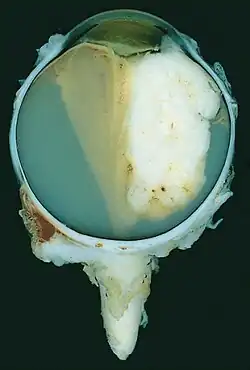

Enukleation

Bei fortgeschrittenem Krankheitsstadium kann der Tumor nur noch durch die Entfernung des betroffenen Auges vollständig beseitigt werden. Bei dieser Enukleation wird das Auge mit einem möglichst großen Teil des Sehnerven (über den eine Ausbreitung von Metastasen ins Gehirn möglich ist) operativ entfernt. Die Augenmuskeln und der übrige Inhalt der Orbita bleiben dabei erhalten. Tumor und Sehnerv werden im Anschluss an die Enukleation histologisch untersucht, um eine eventuelle Metastasierung feststellen zu können.

Im Anschluss an die Entfernung des Augapfels wird ein Implantat in die Augenhöhle eingesetzt, auf das eine Augenprothese aufgesetzt werden kann.